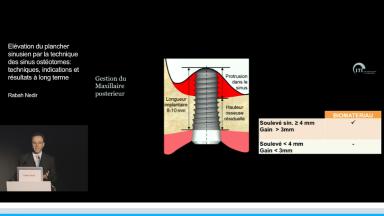

Cette présentation expose les techniques d’augmentation sinusienne, en particulier celle d’élévation du plancher sinusien par voie crestale à l’aide d’ostéotomes.

La réhabilitation implantaire du maxillaire postérieur fait face à deux difficultés : une hauteur osseuse infra-sinusienne fréquemment diminuée ainsi qu’une faible densité osseuse. Dans un souci permanent de simplification des thérapeutiques chirurgicales l’utilisation de la technique des ostéotomes permettrait, selon Dr Nedir, de traiter un plus grand nombre de patient et ce de manière prédictible. Il détaille l’utilisation de cette technique dans sa pratique privée et au travers de différentes études cliniques réalisées avec un suivi allant jusqu’à 10 ans.

- de savoir poser l’indication de la technique des sinus ostéotomes

- d’établir un protocole d’utilisation de la technique des ostéotomes avec et sans utilisation de biomatériaux

- de connaitre les limites de cette technique, laissant alors place à la technique par voie latérale